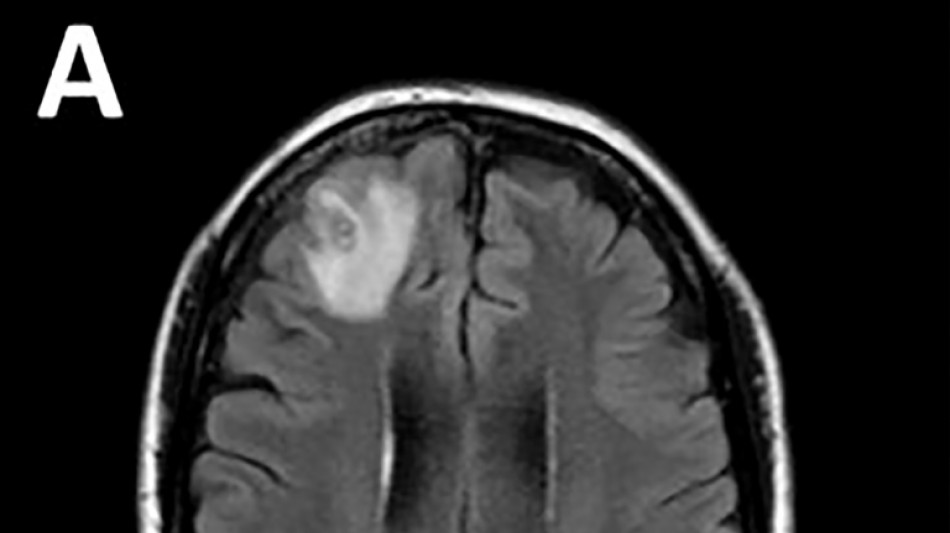

Desconcertados, los médicos realizaron una resonancia magnética a una mujer australiana de 64 años después de que comenzara a sufrir lapsos de memoria y notaron una "lesión atípica" en el frente de su cerebro.

Era una lombriz de ocho centímetros llamada Ophidascaris robertsi, que según investigadores son parásitos comunes en canguros y pitones diamantina pero no en humanos.